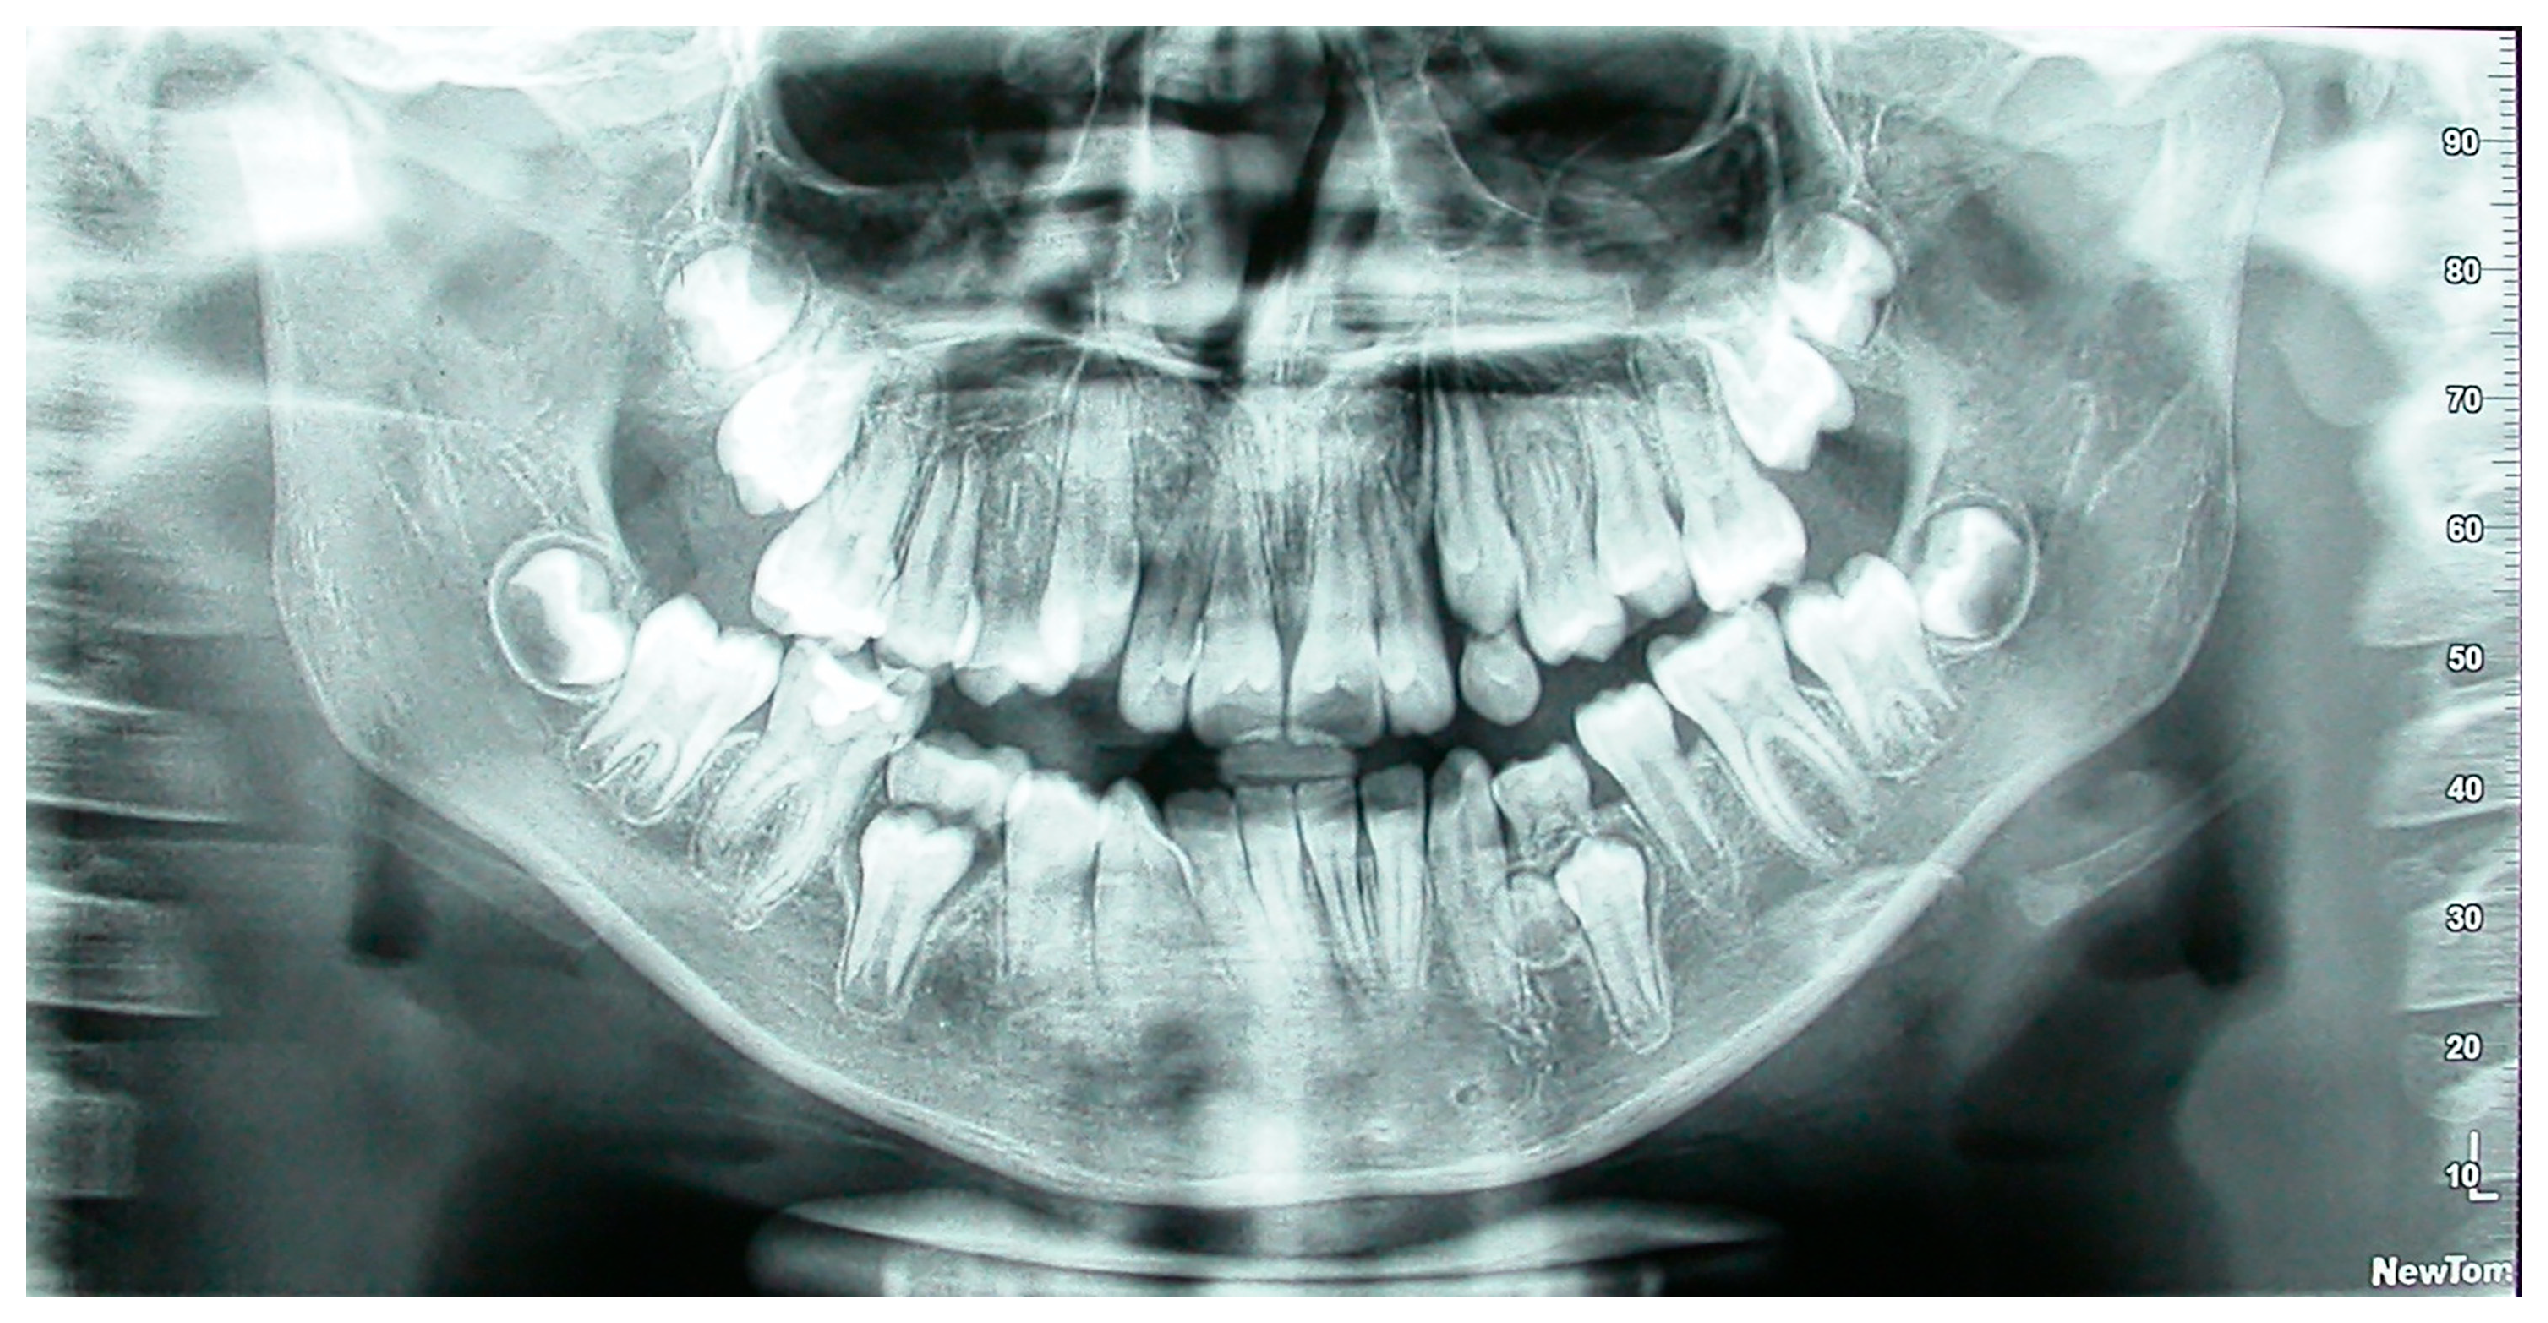

Figure 1. Panoramic radiograph of a patient with supernumerary mandibular left right premolar.